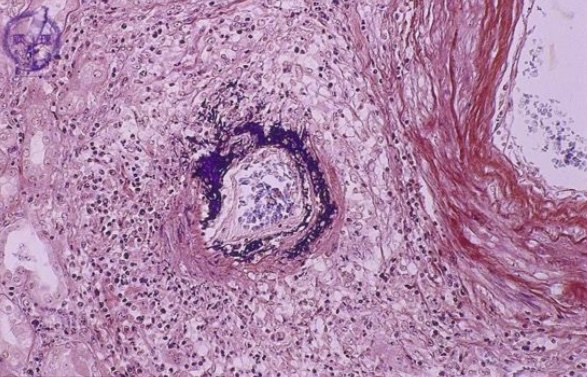

Cholesterol clefts

Fibrinoid

Sphingomyelin